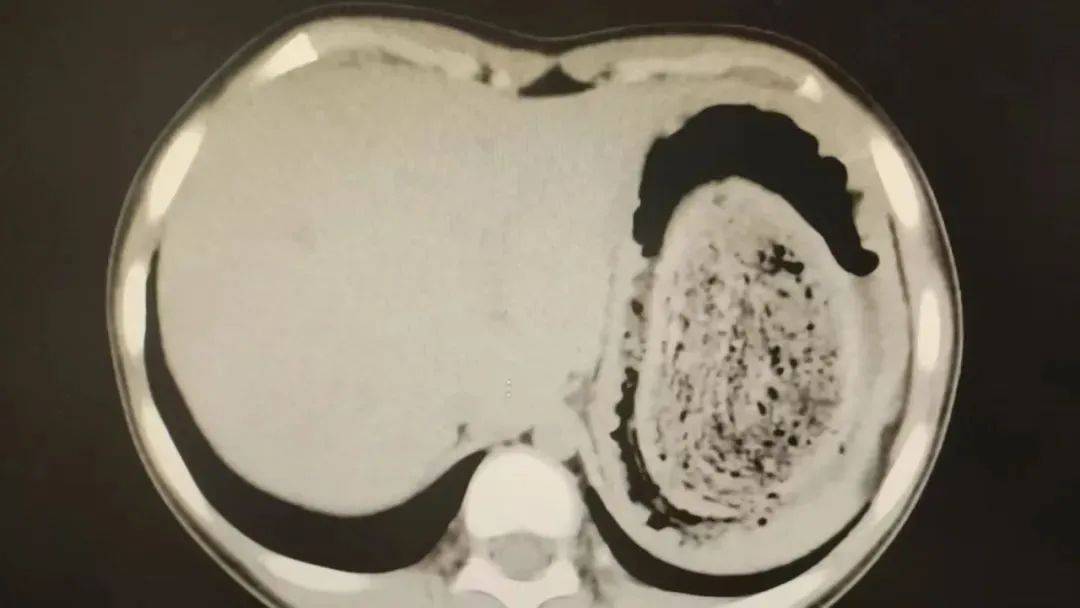

结果出来时,医生都惊呆了:小可的胃里,塞满了成团的头发,几乎占了胃容量的四分之三皇冠信用網在线注册。大量不能消化的物质,在胃酸的作用下发生变性,并与食物及其他物质结合形成团块,慢慢变成坚硬的“胃石”。

为了避免用手术方式去除头发团, 陈攸涛先让小可喝可乐软化“胃石”,再通过胃镜辅助取出头发,整个过程花了十几个小时,清理出的头发装了 两大盆皇冠信用網在线注册。